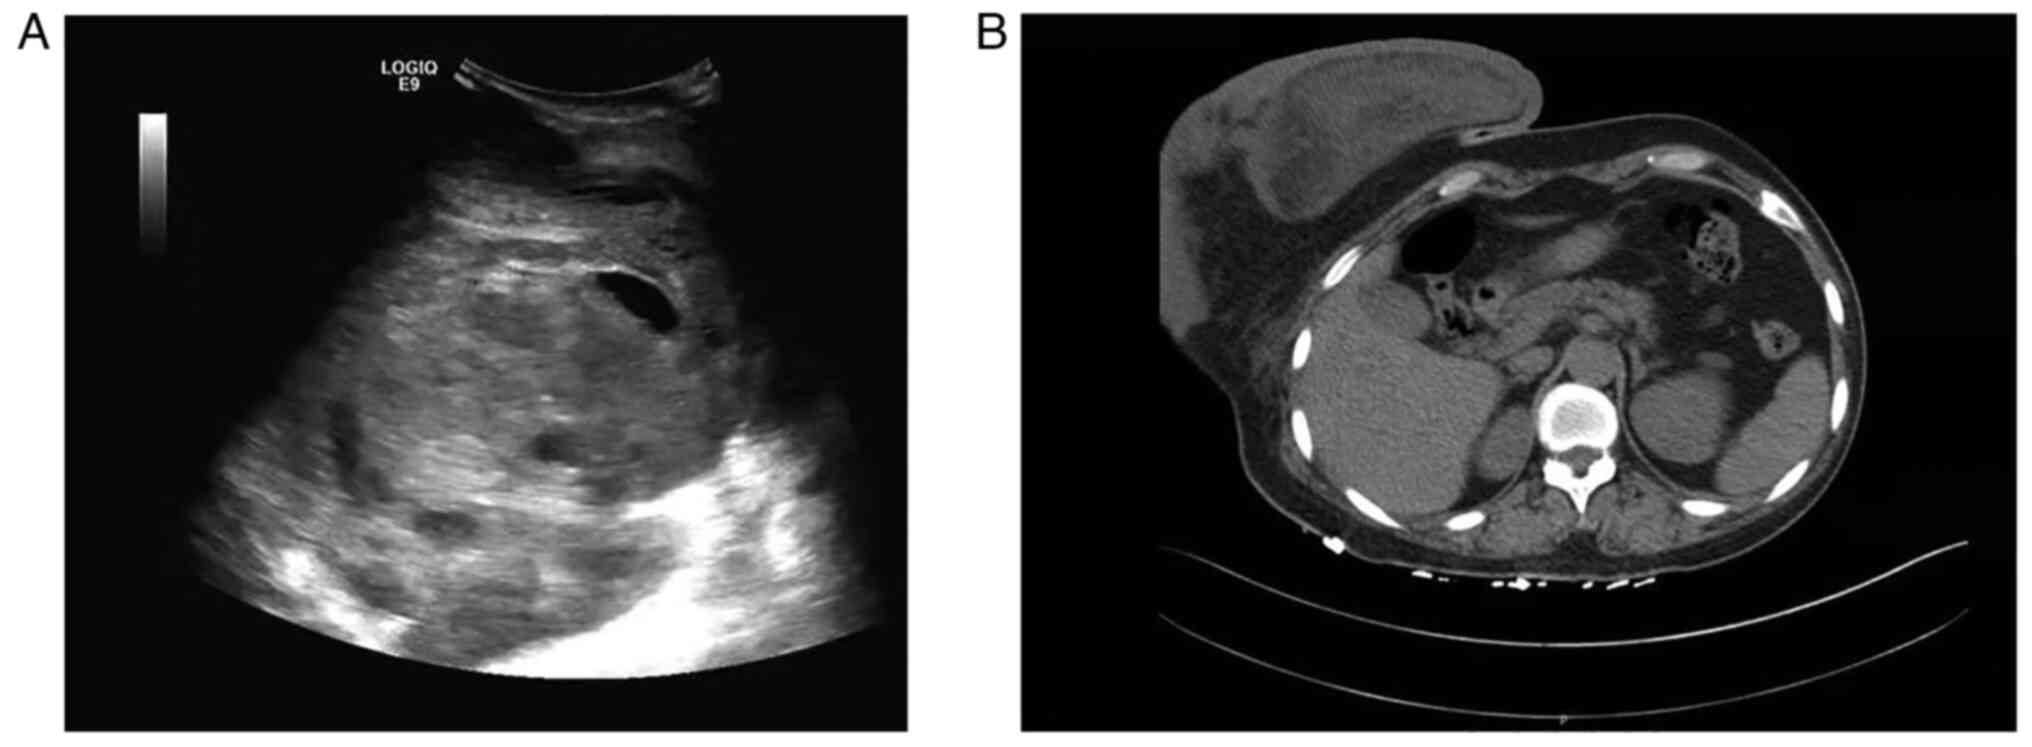

Physical examination revealed a giant hard mass (~25×25×10 cm). The lesion occupied the entire right breast without skin retraction or other skin alterations. Nipple discharge and palpable axillary or supraclavicular lymph nodes were not observed. The liver [glutamic-pyruvic transaminase, 16 U/l (normal range, 0–40 U/l); glutamic oxalacetic transaminase, 15 U/l (normal range, 0–40 U/l)] and kidney [creatinine, 56 µmol/l (normal range, 41–81 µmol/l)] functions were normal, and the serum tumor marker levels were within the normal range [carcinoembryonic antigen, 0.70 ng/ml (normal range, 0–5 ng/ml); carbohydrate antigen 153, 6.25 U/ml (normal range, 0–19 U/ml]. Breast ultrasonography revealed a giant, well-circumscribed, heterogeneous and hypoechoic lesion with central and peripheral blood flow (Fig. 1A). The diameter of the lesion was not measured using breast ultrasonography due to its size. Computed tomography revealed a large heterogeneous tumor of ~25×25×10 cm in the right breast (Fig. 1B). Mammography and magnetic resonance imaging were not performed, as the lesion was too large.

Figure 1.

Ultrasonography and CT expression of the breast solitary fibrous tumor. (A) Ultrasonography revealing a giant, well-circumscribed, heterogeneous and hypoechoic lesion with central and peripheral blood flow. (B) CT showing a giant heterogeneous lesion in the right breast. CT, computed tomography.